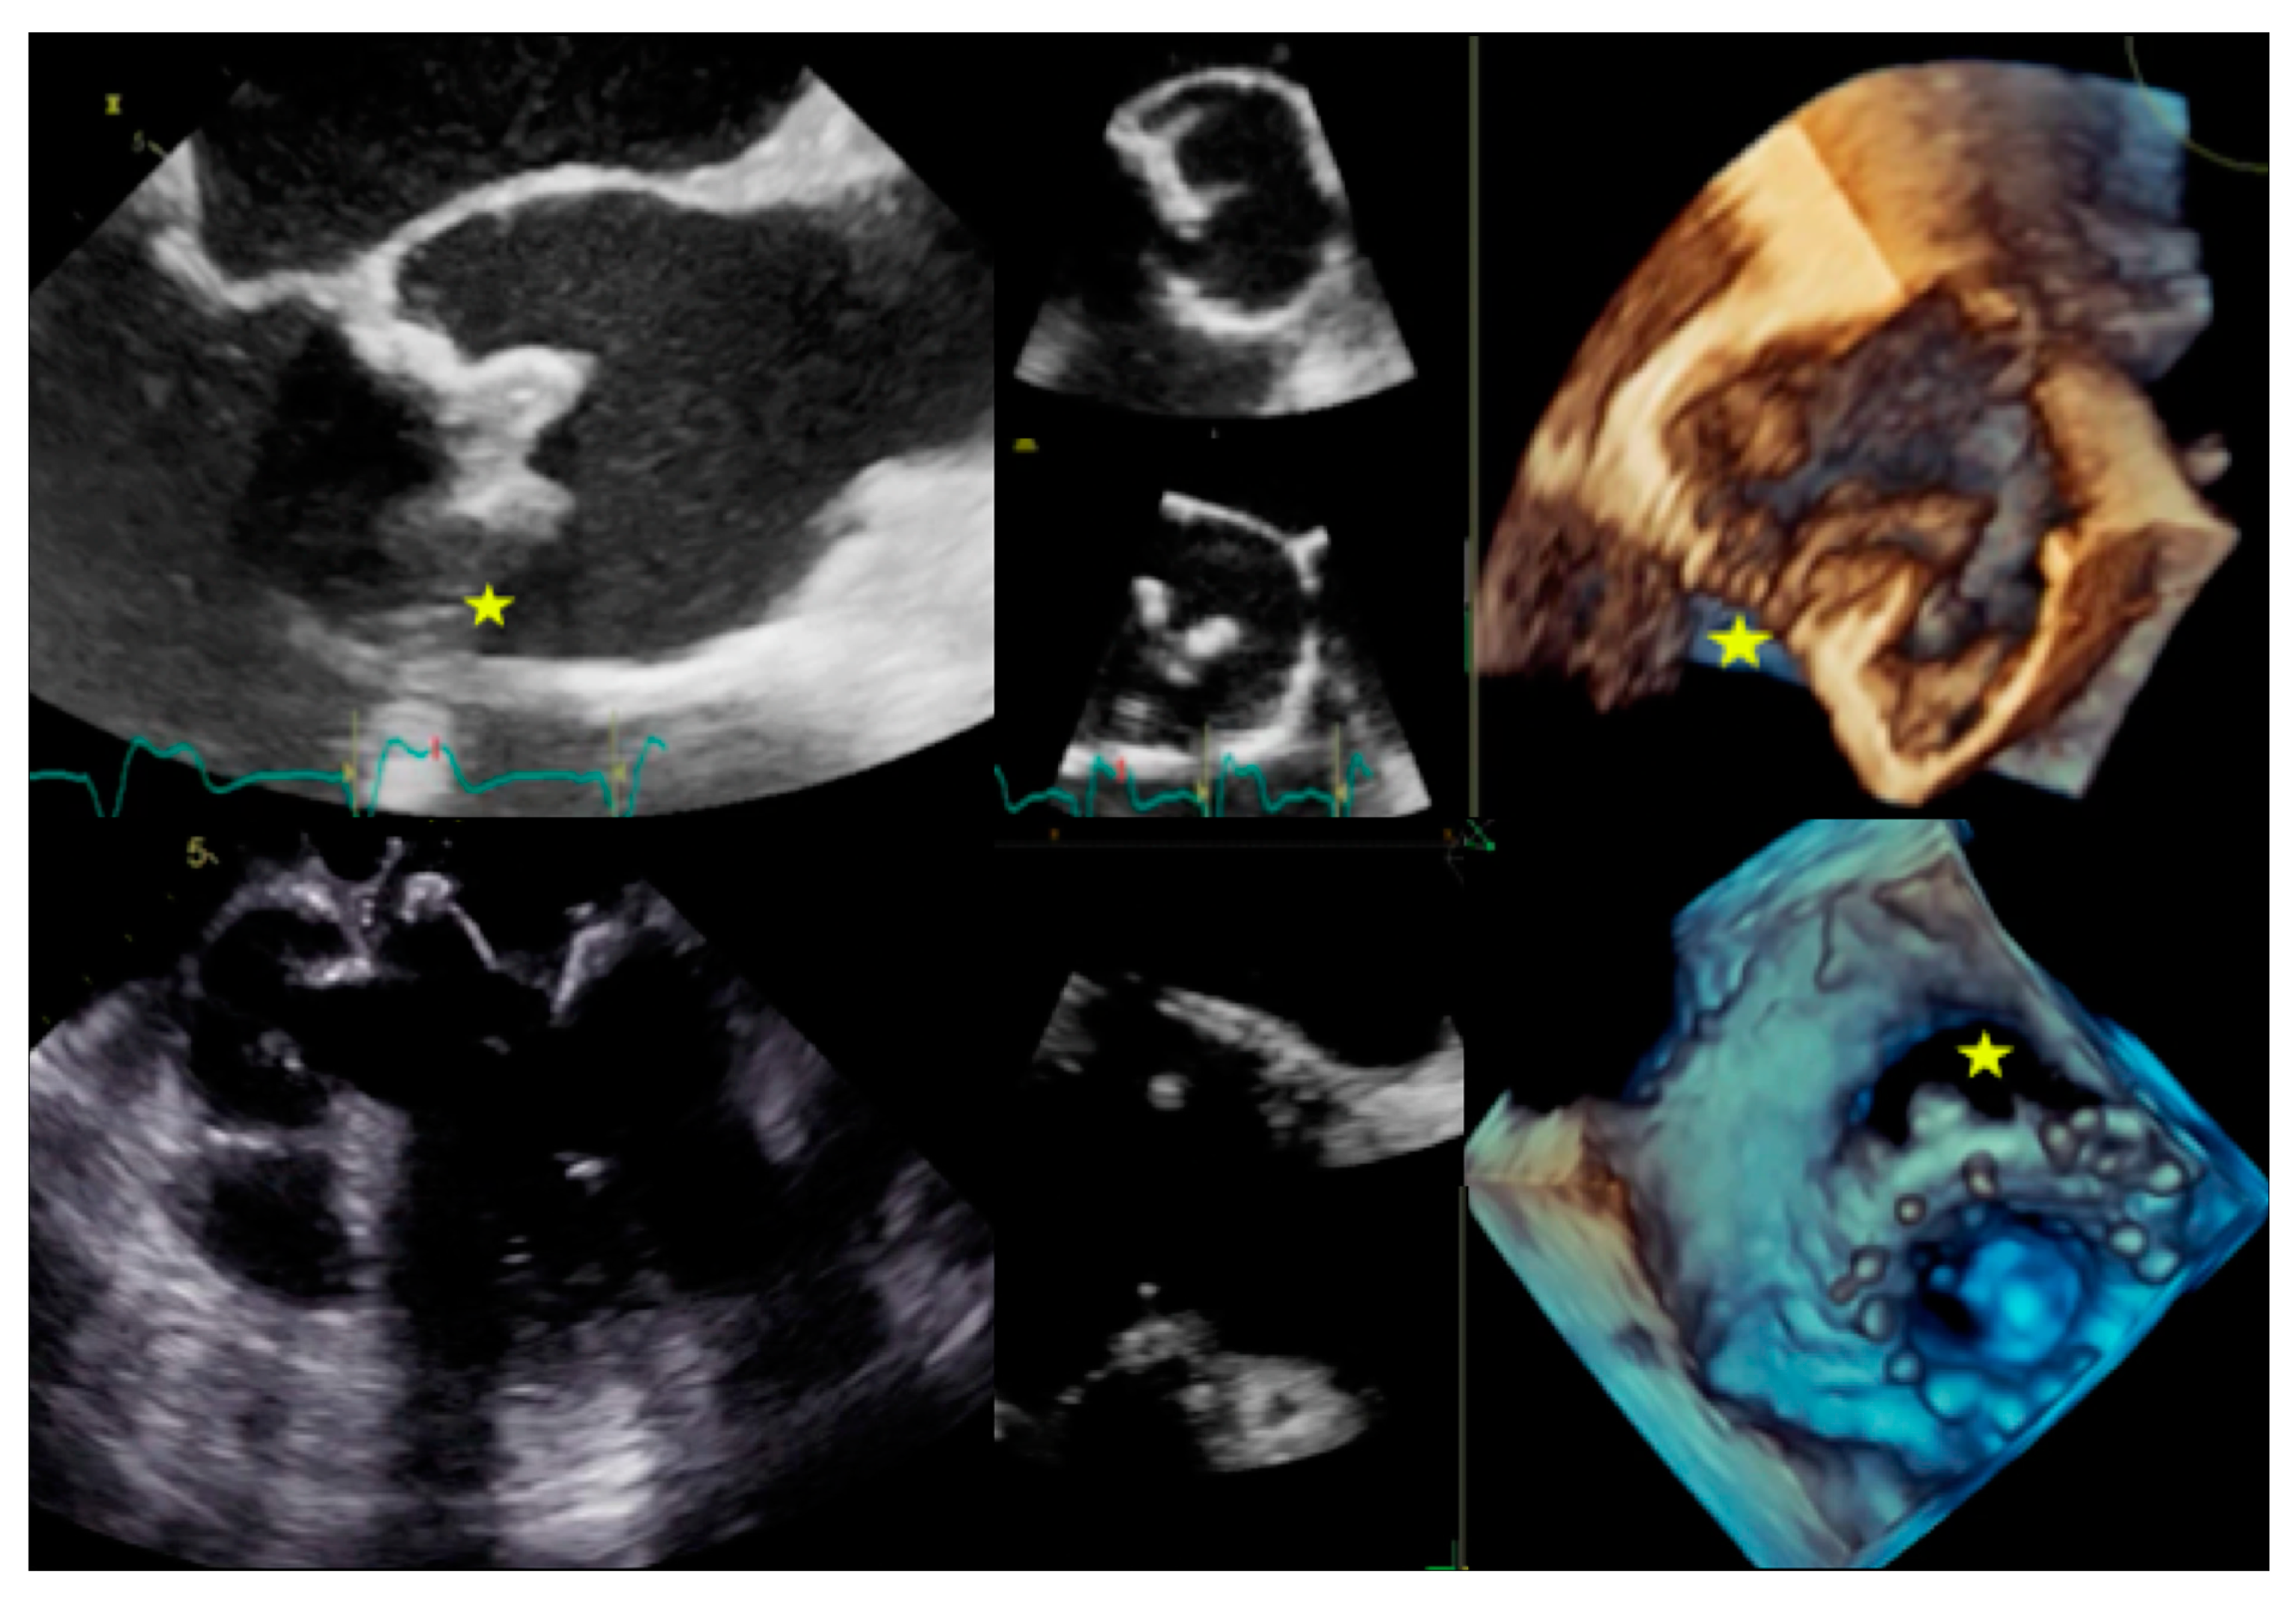

| Left-sided IE | Good visualization of mitral and aortic valve. Valvular dysfuction assessment. Identification of complication (i.e., valvular regurgitation). | Difficult differential diagnosis in presence of marantic vegetations or high calcification. | Detection of vegetations and valve perforation. Assessment of perivalvular extent of disease (abscesses, pseudoaneursysm, fistula). | Inferior to TTE/TOE in detecting small vegetations (<2 mm). | Prognostic assessment: simultaneous detection of embolism, metastatic lesions and portal of entry. | Limited sensitivity for small vegetations. | Evaluation of distant emboli and portal of entry. | Limited role because of low sensitivity for small vegetations. | Capability to assess vegetations (inferior to TTE/TOE). Capability to assess local complications. Independent by acoustic window. May detect concomitant myocardial inflammation. | Not included in current guidelines for IE diagnosis. |

| Right-sided IE | TTE generally provides good visualization of tricuspid valve. TOE is useful in the assessment of IE related to CHD. | Pulmonary valve is difficult to assess. | ||||||||